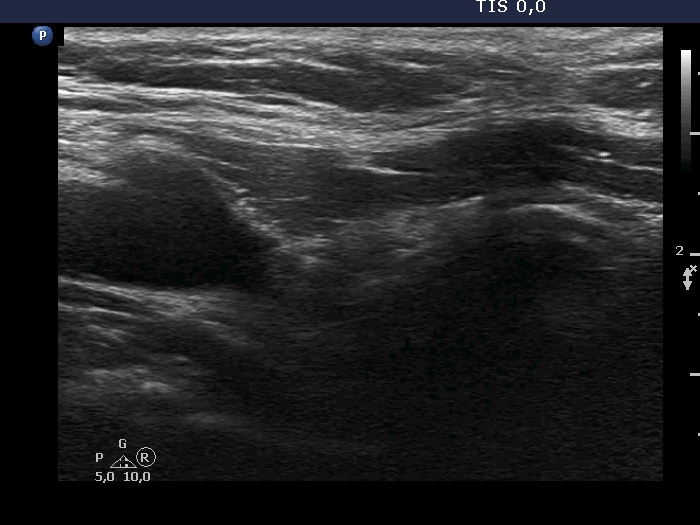

First examination (first two rows of images):

Clinical presentation: A 39-year-old woman went with her father to my consulting and she decided to request a thyroid examination. She has been treated with lithium for depression for more than 10 years. Two years after the initiation of antidepressant treatment hypothyroidism has developed. The patient was stopping the daily 50 microgram levothyroxine therapy one year ago because she felt no effect of the replacement treatment. Except for regular TSH determinations no other thyroid tests has been performed ever.

Palpation: both lobes were firm. There was a firmer nodule in the lateral part of the left lobe.

Laboratory tests: TSH 4.07 mIU/L, FT4 11.2 pM/L, aTPO 206 U/mL on daily 900 mg lithium.

Ultrasonography. The thyroid was minimally-moderately hypoechoic and presented pronounced fibrotic changes. The left lobe had several hypoechoic nodules having cystic areas and numerous microcalcifications. Isolated microcalcifications were found in large numbers outside the nodules. The tumor showed irregularly increased intranodular vascularization.

Cytology. Papillary cancer.

Histopathology. Multifocal papillary cancer in the left lobe. The diameter of the largest focus was 20 mm. There were numerous smaller tumor foci, less than 2 mm in diameter.

Comments.

The ultrasound presentation is suspicious of invasive spread.

It is worth comparing the presentations of fibrosis in the right lobe and that of the microcalcifications outside the nodule in the left lobe.